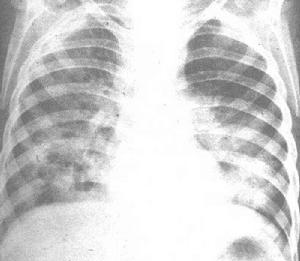

間質性肺炎X線檢查 實驗室檢查:血液檢查:間質性肺病肺泡結構中炎性和免疫細胞異常與肺外其他病變無關聯,許多患者血沉增速,或血液免疫球蛋白增高,與肺纖維化亦無密切關聯。有些患者血清中可查到免疫複合體,是從肺臟產生而溢出的。有一部分患者類風濕因子、抗核抗體陽性,部分患者血清出現抗肺膠原抗體。動脈血氣分析:由於潮氣量減低,呼吸頻率增高,呼吸淺速,肺泡通氣量不足,導致通氣/血流比例降低,發生低氧血症,但動脈血二氧化碳分壓正常。運動後血氧分壓明顯下降。支氣管肺泡灌注檢查:套用纖維支氣管鏡插入左肺舌葉或右肺中葉,以生理鹽水沖入灌洗,獲得支氣管肺泡灌洗液。將灌洗液作細胞學和非細胞成分的測定。本法具有以下優點:①灌洗液的細胞學檢查能真實地反映肺泡炎肺泡結構中的炎性和效應細胞的類型與數目。②各種間質性肺病的診斷與鑑別診斷。非吸菸人灌洗液的細胞總數為(0.2~0.5)×10E4/ml 其中肺泡巨噬細胞占85%~90%,淋巴細胞約占10%,中性粒細胞及嗜酸粒細胞僅占1%以下,細胞總數多由肺泡巨噬細胞的增加而增加,而細胞種類的變化在ILD 時有診斷意義。如過敏性肺泡炎、結節病、慢性鈹肺時淋巴細胞顯示明顯增加。膠原病伴肺間質纖維化時也可見淋巴細胞增加。而細菌性肺炎、氣道感染以及ARDS 時嗜中性粒細胞增加。閉塞性細支氣管炎伴機化性肺炎時可出現淋巴細胞、粒細胞的增加。支氣管肺泡灌洗液的淋巴細胞中T 細胞占70%~80%,B 細胞占10%~20%,而ILD 中的結節病、過敏性肺泡炎、慢性鈹肺則T 細胞增加。一直想用標記T 細胞亞群或T 細胞、B細胞的活化程度解釋ILD 的活動性和預後。僅見結節病時T細胞數及活化T 細胞數的增加與病情的進展情況相關。此外在特發性肺間質纖維化時活化的B 細胞增加則提示病情的進展,淋巴細胞增多則對激素治療效果較好,其預後也較好。

間質性肺炎確診圖 2.肺功能檢查 此項檢查僅是功能的診斷,而非病理診斷,在早期階段,肺功能檢查可以完全正常,當病情進展才可能出現肺功能檢查的異常。ILD 最顯著的肺功能變化為通氣功能的異常和氣體交換功能的降低。通氣功能是以限制性通氣障礙為主、肺活量減少、殘氣量隨病情進展而減少,隨之肺總量也減少。第1s 時間肺活量(FEV1.0)與用力肺活量(FVC)之比即1s 率出現明顯升高,如已達到90%則支持ILD 的診斷。ILD 的早期可有小氣道功能障礙,其V50、V25均降低ILD形成纖維化後而出現V50、V25 增加。ILD 的早期還可以出現氣體交換功能障礙,如彌散功能(DLCO)較早期即有降低,一旦X 線胸片發現間質性改變,DLCO 則已降低50%以下。肺功能改變與肺部病變二者的相關性,在病變輕微者極差,病情嚴重者相關性較好。凡肺功能嚴重損害者,肺部病變肯定嚴重。在肺功能的各項檢測中,容量-壓力曲線測驗和運動時動脈血氧的變化,僅在反映肺纖維化的嚴重程度上最為敏感。肺功能檢查對於ILD 的早期診斷與判定預後是非常有用的,特別是動態觀察VC、FEV1.0、DLCO 等指標。至於肺功能檢查能否判斷激素或免疫抑制劑治療ILD 的療效,有不同的看法,僅以肺功能的變化評價療效是不夠的。